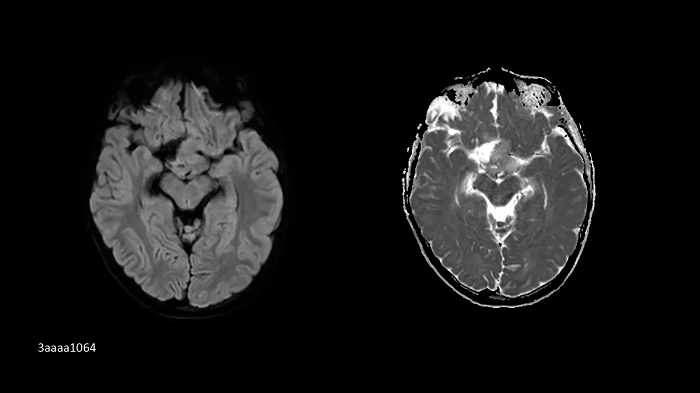

Neurology

SMS RESOLVE

Exceptional diagnostic performance with RESOLVE using high-resolution DWI and DTI of the brain, as well as increased efficiency with Simultaneous Multi-Slice (SMS).

SMS RESOLVE

PAT 2 SMS 2, b1000| 1.0 × 1.0 × 4.0 mm3 | TA 2:32 minutes

Image Credit: Customer contribution from Austria